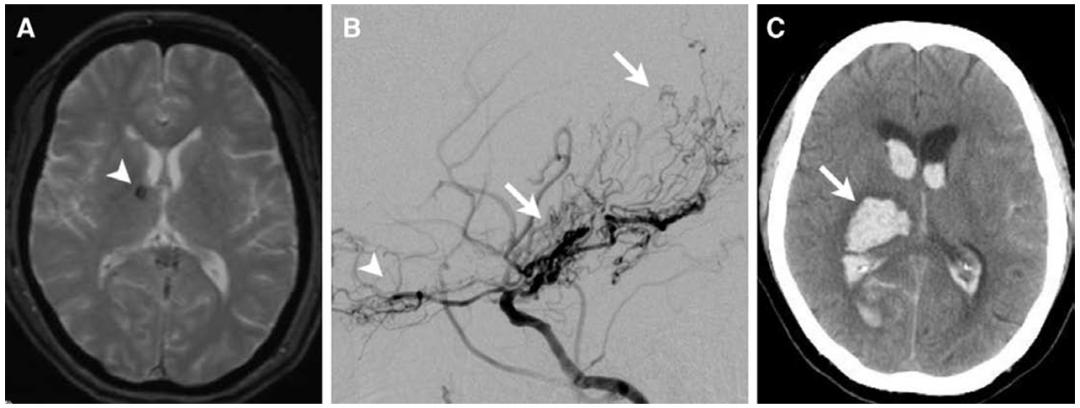

MMD 临床表现为短暂性脑缺血发作 T2*WI示右侧丘脑静态的CMBs(A)。DSA示明显烟雾样血管起源于豆纹动脉、脉络膜前动脉、脉络膜后动脉和筛动脉(B)。1周后,CT示右侧丘脑出血破入脑室(C)。